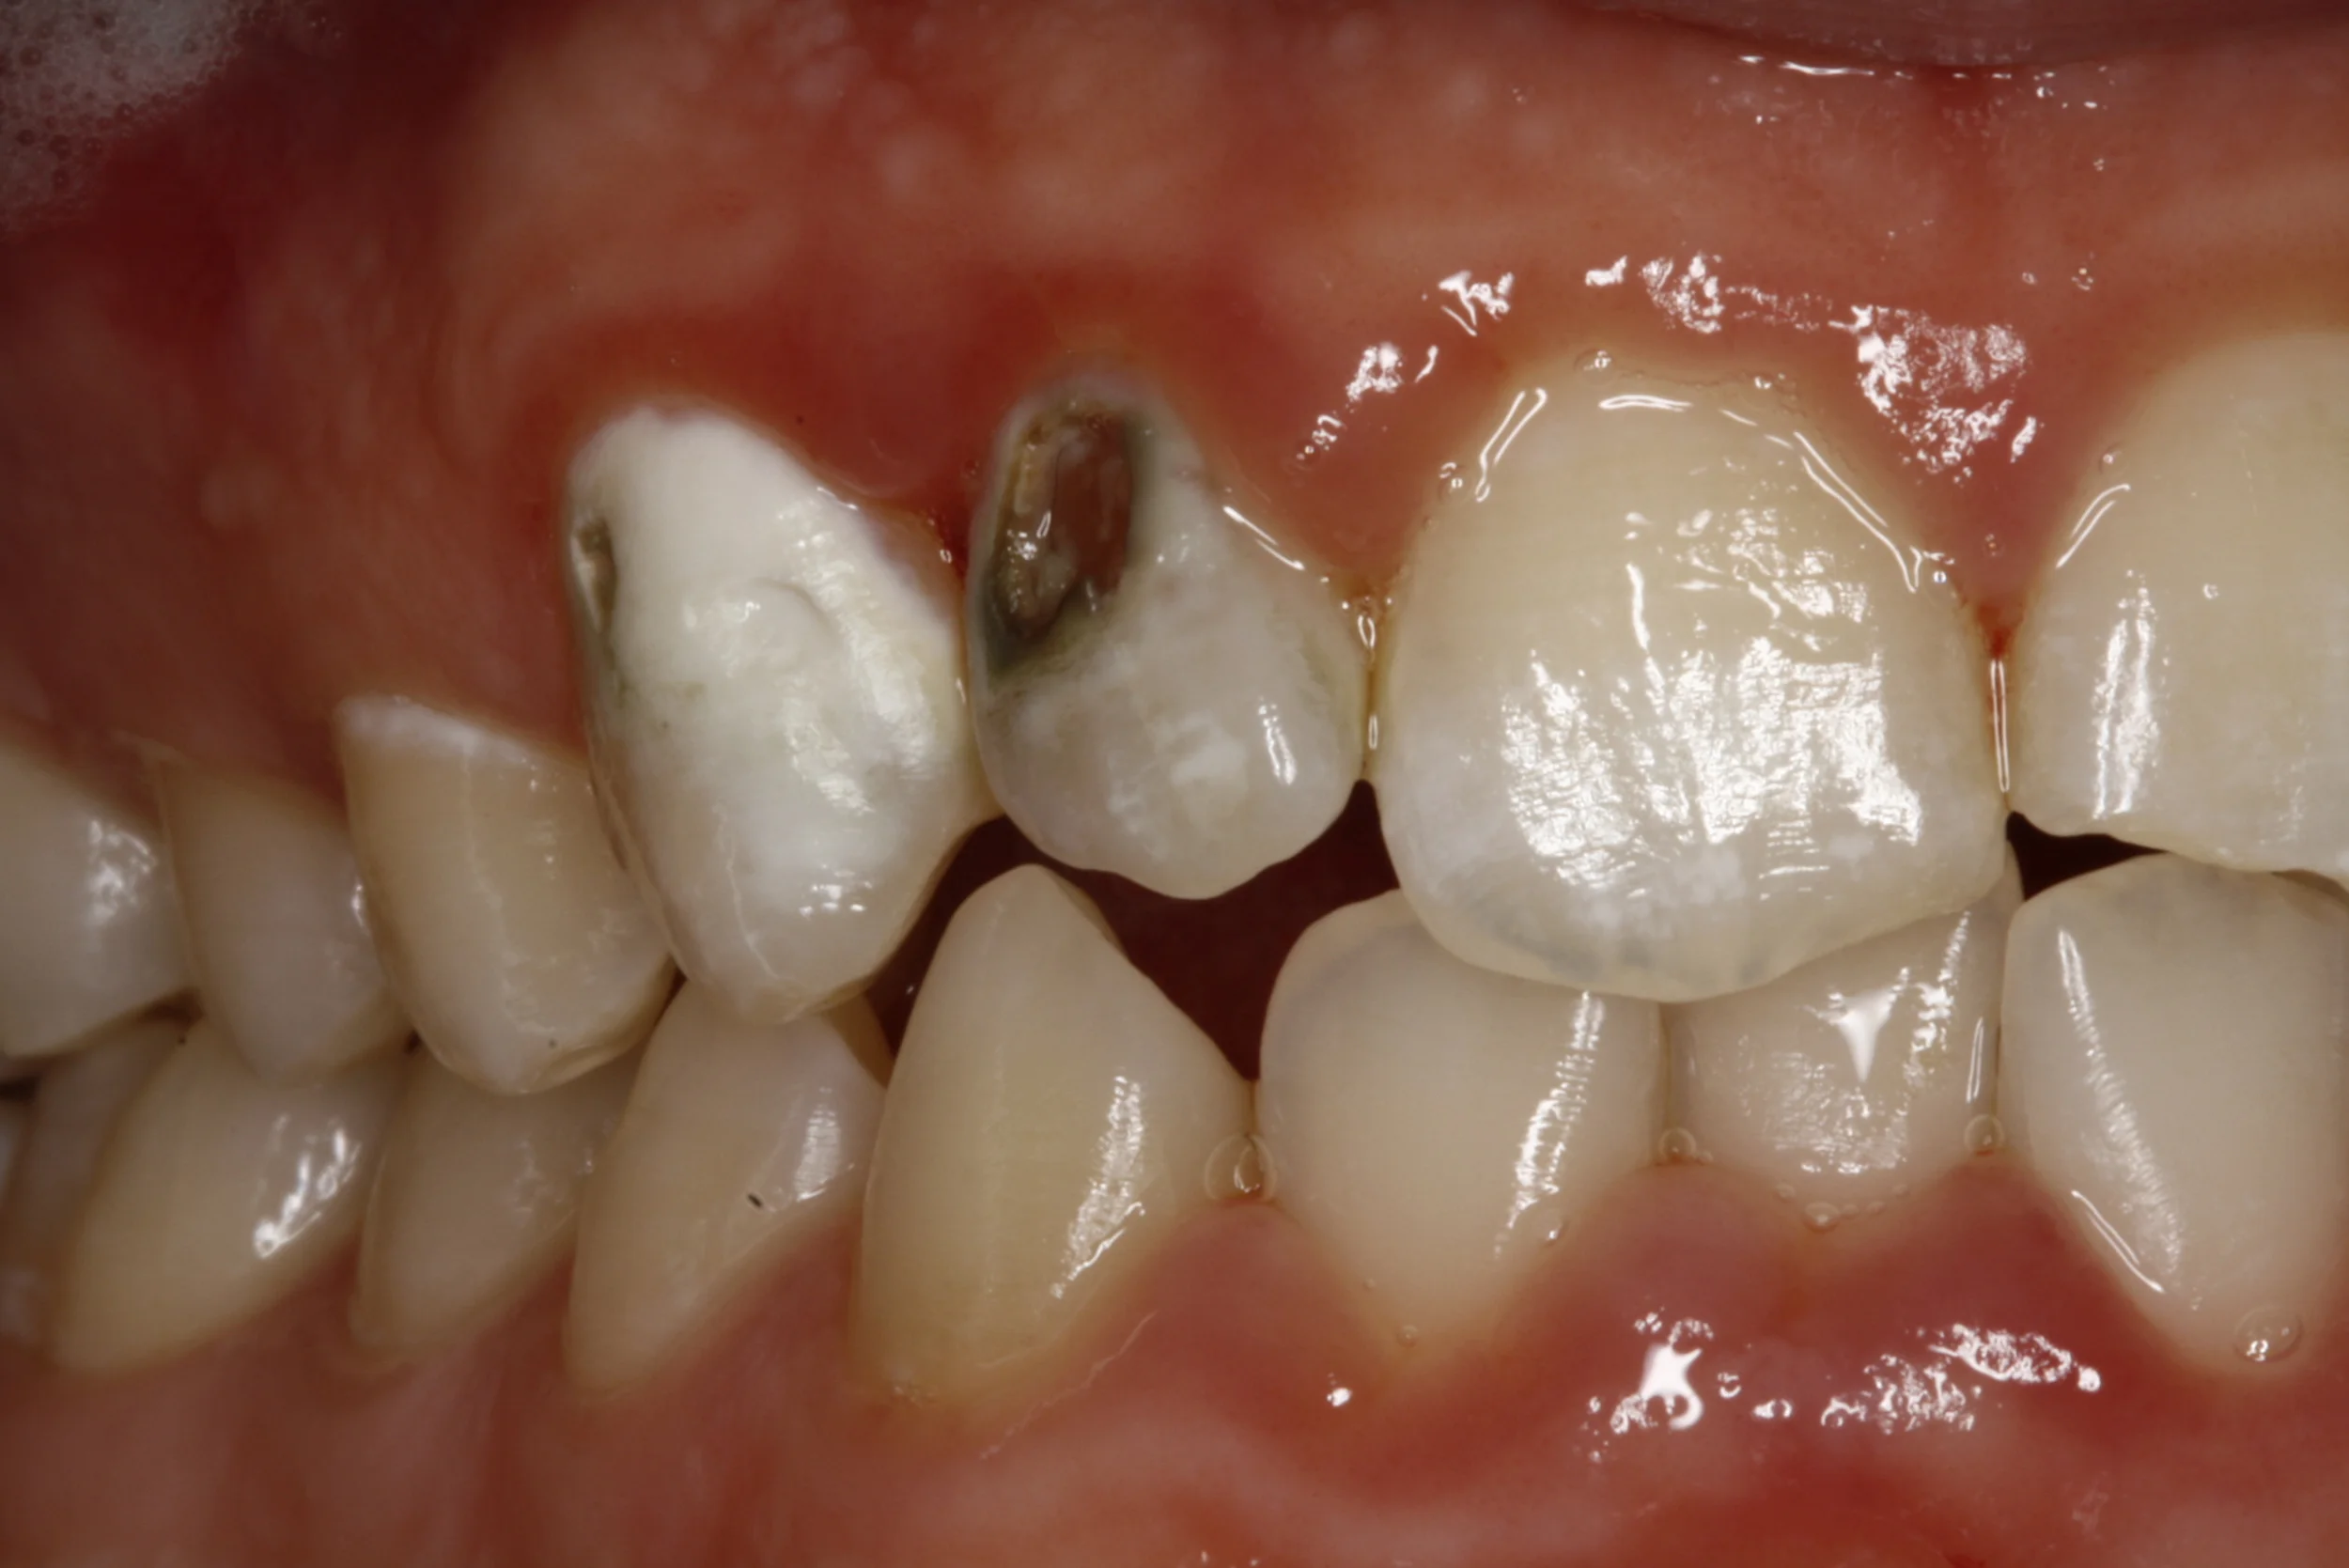

Case - Fillings

Fillings showcase